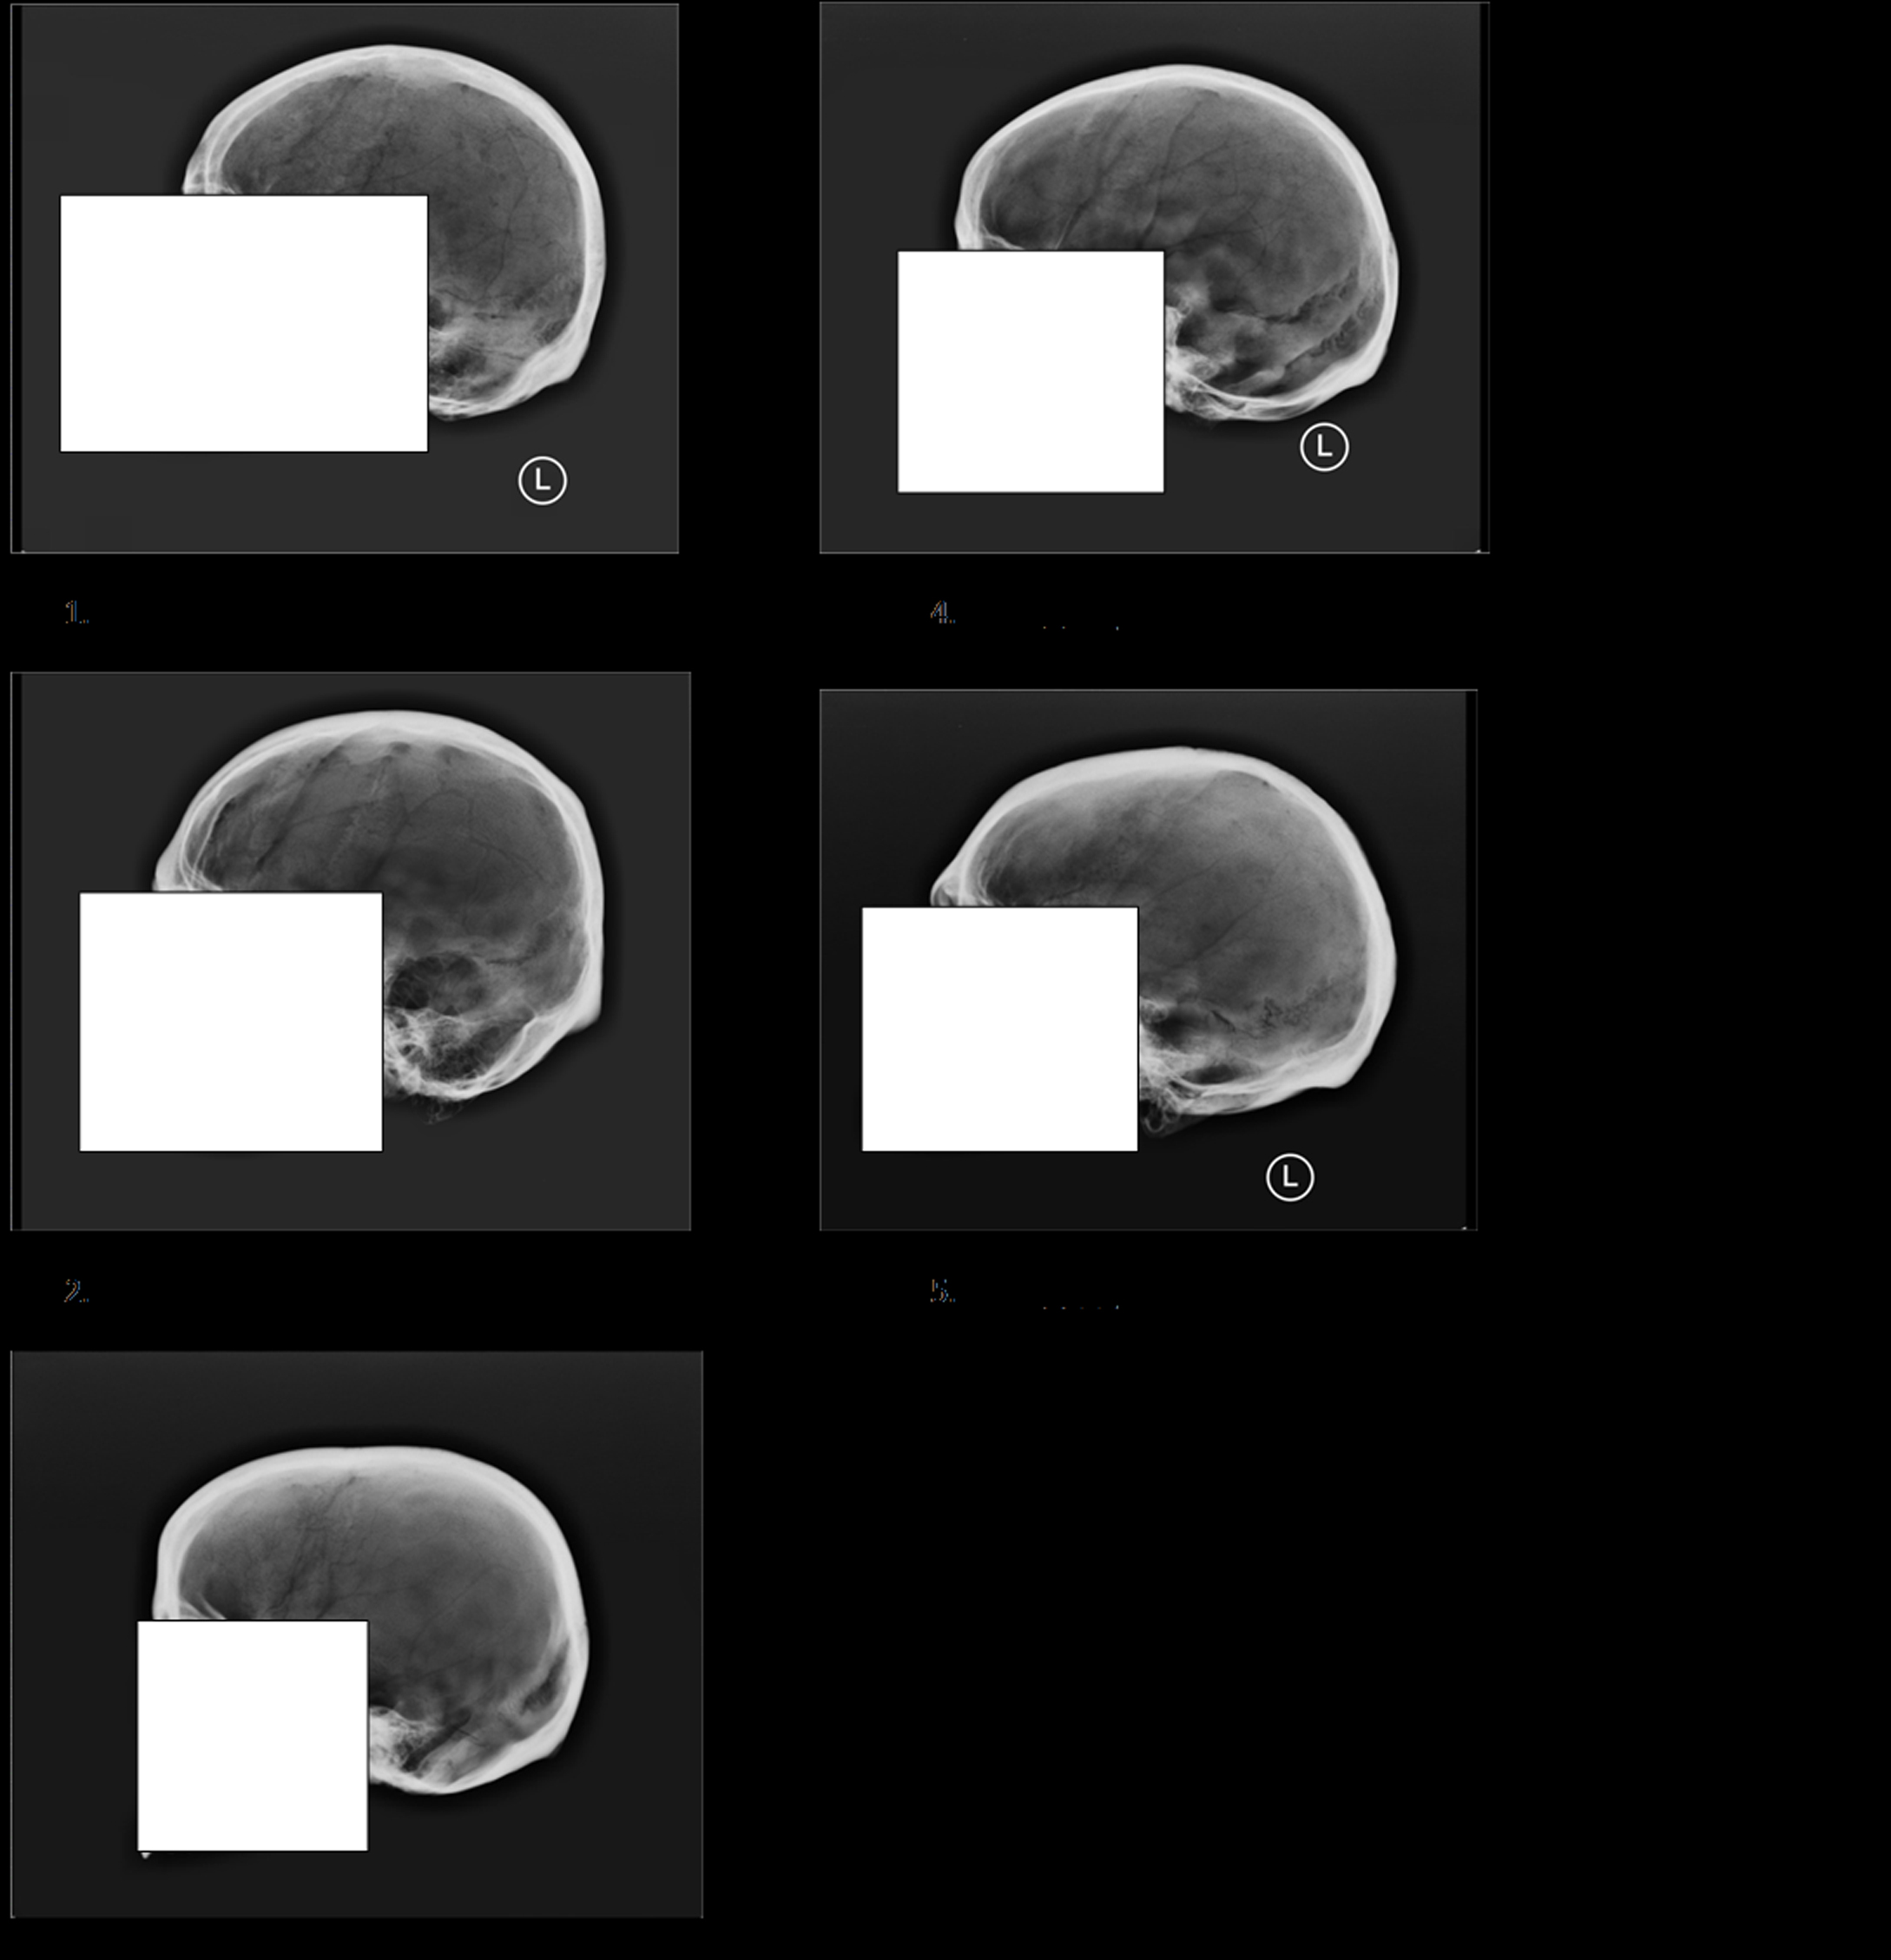

Specifically, only 56 percent of forensic anthropology Ph.D.s (the bone experts) could correctly match two images of the same skull, based solely on the “cranial vault outline” of the skull – the side profile of the skull running from just above the bridge of the nose to the point where the skull and neck meet.

下面,您将发现14个andemortem骷髅X射线和五个后骨折X射线。您需要将5次淘汰的X射线与适当的AnteMortem X射线匹配,有效地建立正面ID。让我们看看你是怎么做的!

第五个邮件X射线编号如下:1 =左上角,2 =左中心,3 =左下角,4 =右上角,5 =右下方。您可以单击图像以放大它们,答案位于帖子的底部。

后期X射线